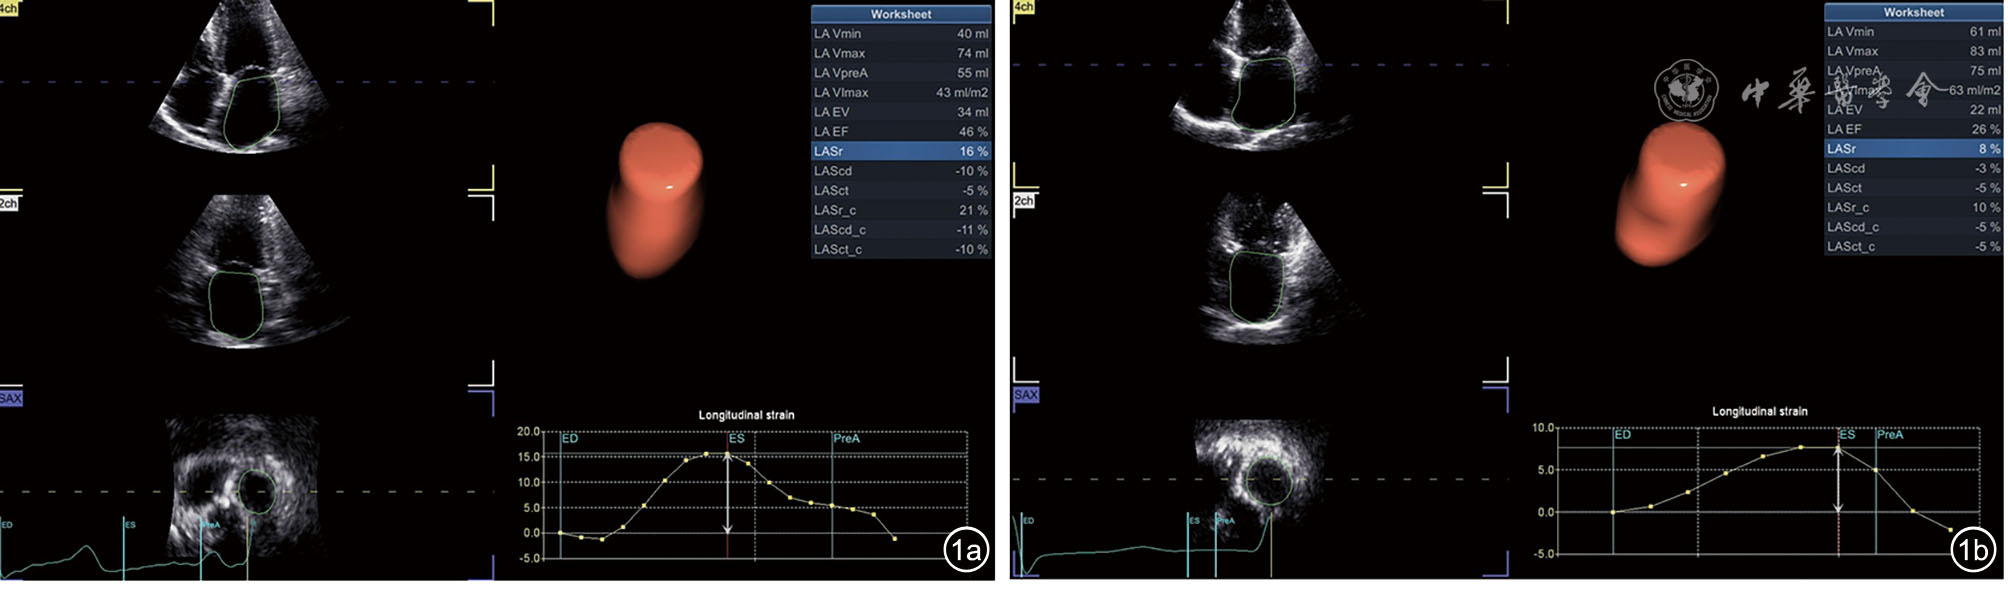

A total of 109 HFpEF patients admitted to the First Affiliated Hospital of Zhengzhou University from December 2023 to December 2024 were enrolled and divided into a paroxysmal AF group (n=40) and a non-AF group (n=69). Clinical data were collected, and echocardiographic parameters (2D, color Doppler, and tissue Doppler) were measured. 4D Auto LAQ was applied to obtain LA volumetric and strain parameters [left atrial minimum volume (LAVmin), left atrial maximum volume index (LAVImax), left atrial pre-systolic volume (LAVpreA), left atrial stroke volume (LAEV), left atrial total ejection fraction (LAEF), left atrial systolic longitudinal and circumferential strain (LASr/LASr-c), left atrial pipeline longitudinal and circumferential strain (LAScd/LAScd-c), and left atrial systolic longitudinal and circumferential strain (LASct/LASct-c)]. Differences in these parameters between the two groups were assessed using the t-test. Receiver operating characteristic (ROC) curve analysis was performed to assess the overall diagnostic efficacy of left atrial parameters for HFpEF combined with paroxysmal AF and calculate the optimal cut-off value. Logistic regression analysis was utilized to analyze the correlation between left atrial parameters and the occurrence of paroxysmal AF in patients with HFpEF.

Compared to the non-AF group, the paroxysmal AF group showed increased LAVmin, LAVImax, and LAVpreA [(64.08±16.44) ml vs (36.67±15.68) ml; (51.68±11.56) ml/m2vs (38.13±10.38) ml/m2; (71.93±16.80) ml vs (50.17±16.99) ml], and the differences were statistically significant (t=-6.610, -6.297, and -5.660, respectively, all P<0.001). The absolute values of LAEV, LAEF, LASr, LASr-c, LAScd, LAScd-c, LASct, and LASct-c were all decreased [(20.93±6.44) ml vs (27.26±9.28) ml; (25.23±7.88)% vs (43.55±9.70)%; (6.78±3.42)% vs (14.41±4.15)%; (7.60±4.25)% vs (21.25±9.59)%; (-4.93±3.08)% vs (-8.65±3.46)%; (-4.93±3.38)% vs (-10.14±5.60)%; (-1.90±3.39) vs (-5.81±3.26); (-2.83±3.24)% vs (-11.72±5.89)%; all P<0.001). LASr demonstrated the highest diagnostic performance for identifying HFpEF with paroxysmal AF (area under the curve [AUC]=0.928, 95% confidence interval [CI]: 0.875-0.980, P<0.001), with an optimal cutoff value of 8.5%, sensitivity of 72.5%, and specificity of 97.1%. Logistic regression analysis demonstrated that LASr was independently associated with paroxysmal AF in HFpEF patients after adjusting for clinical and other echocardiographic parameters (odds ratio=0.340, 95%CI: 0.137-0.847, P=0.011).